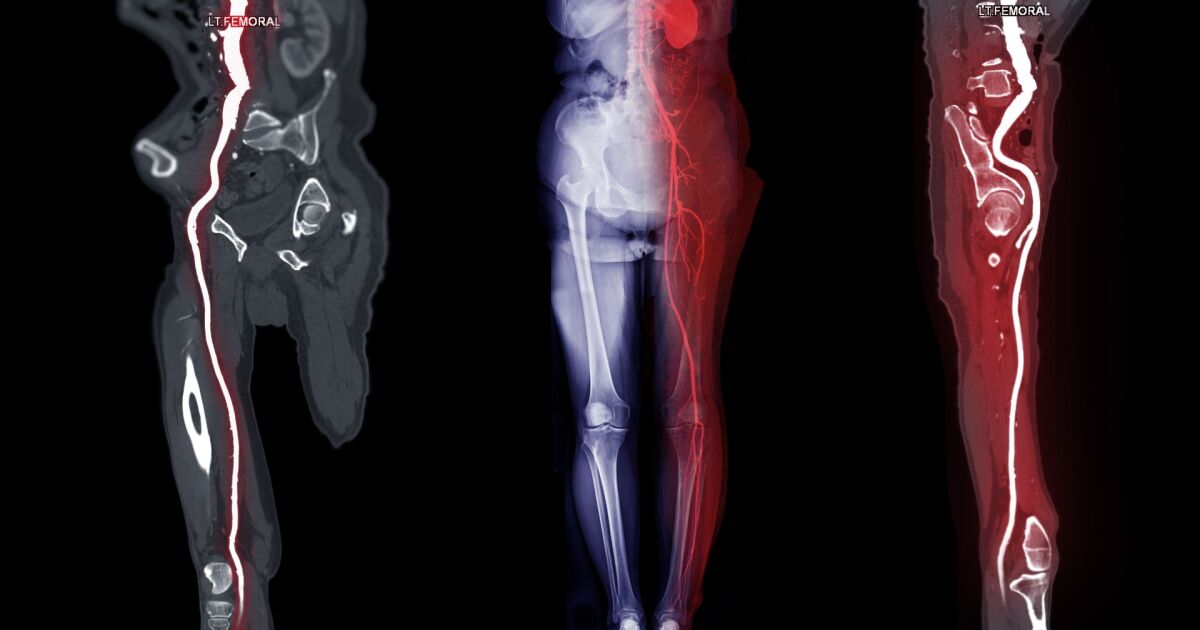

- ангиография – рентгеново изследване с контрастно вещество за откриване на стеснения и запушвания.

Новото устройство комбинира механично отстраняване на плаките (атеректомия) и аспирация (изсмукване) на отпадъчния материал. За разлика от други методи, системата позволява безопасно преминаване през напълно запушени артерии, без предварителни стъпки като използване на водач или разширяване на съда.

Това е особено важно при сложни лезии на феморо-поплитеалния сегмент (областта на бедрената и подколенната артерия) и при пациенти с вече поставени стентове.